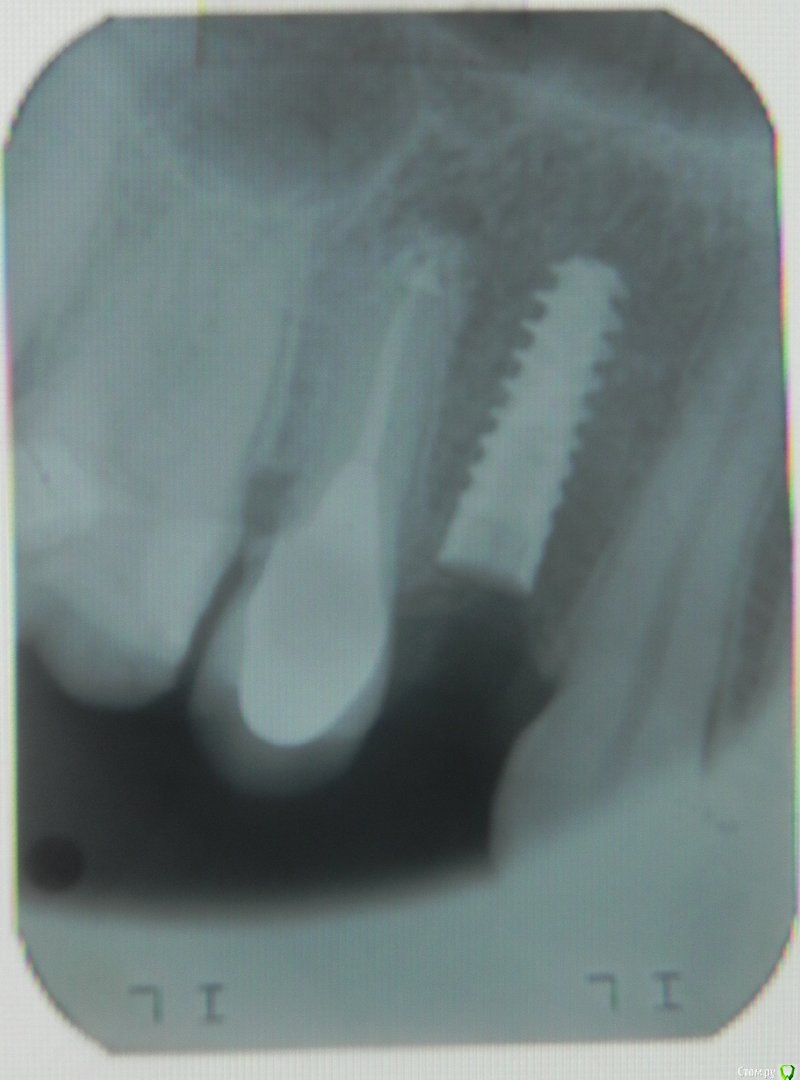

Большой Зеленый Опубликовано 15 июня, 2015 Поделиться Опубликовано 15 июня, 2015 А здесь есть показания?http://s020.radikal.ru/i704/1506/e3/b272f8325772.png 1 Ссылка на комментарий

Kostoprav Опубликовано 15 июня, 2015 Поделиться Опубликовано 15 июня, 2015 тоже был случай, выкрутил) хотя жалоб и не было Ссылка на комментарий

Kostoprav Опубликовано 15 июня, 2015 Поделиться Опубликовано 15 июня, 2015 и вот)переустановил на следующий день Ссылка на комментарий

Kovalov Igor Опубликовано 16 июня, 2015 Поделиться Опубликовано 16 июня, 2015 А здесь есть показания? а кт не делали? ))) вопрос чувствую с загвоздкой Ссылка на комментарий